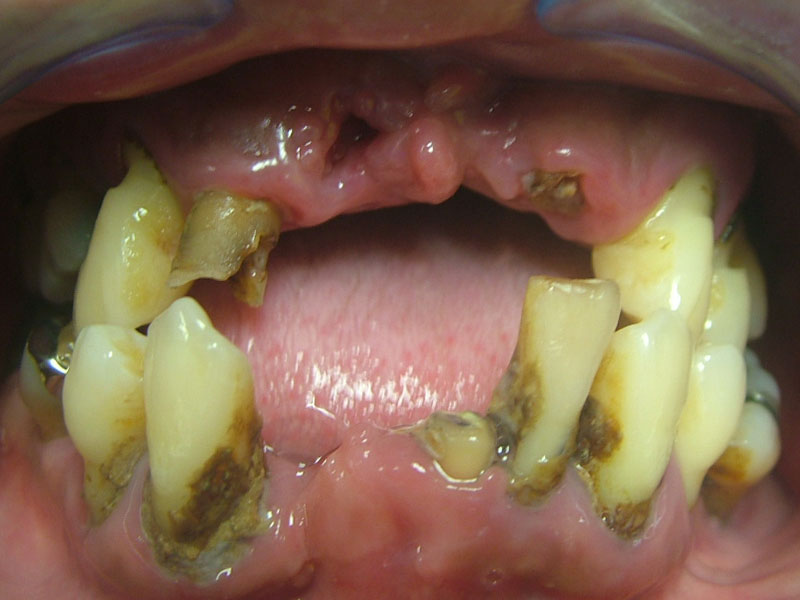

治療前

概要

- 初診:2019年(コロナ禍)

- 主訴:保険外の治療で食べれるように、入れ歯以外の方法で何とかしてほしい。

- 上下のCT解析を行う。(上顎には以前の顔面骨折による治療跡であるチタンのプレート、ボルトが確認できる。左側は慢性の副鼻腔炎を患っている。)

- 上下のクリーニングと歯磨き指導、禁煙指導を徹底的に行う。